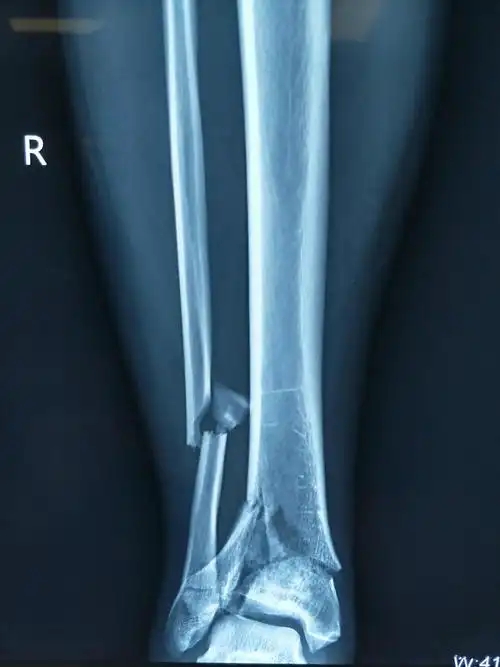

双胫腓骨下段粉碎性骨折求治疗方案

胫腓骨远端粉碎性骨折求手术方案 [病例帖]

原创小腿远端粉碎骨折

左小腿开放性粉碎性骨折病例汇报

一例严重胫骨粉碎性骨折,请大家讨论下一步治疗方案? [病例帖]